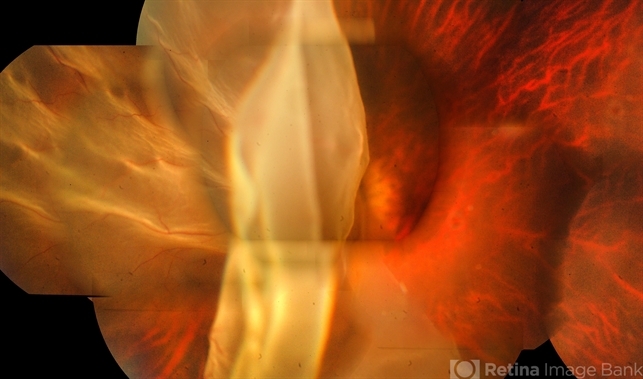

- giant retinal tear

- Giant retinal tear with averted flap and edges.